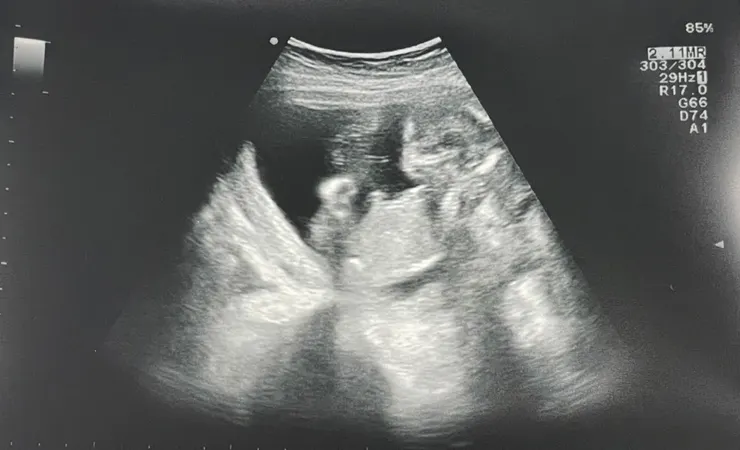

15週 來到第三次健保給付的產檢

醫生叫號~先請我躺著照超音波

來照一下胎兒目前的生長狀態 :)

剛好肚子裡的生物手腳大擺動著

擺動幅度之大讓我們都嚇了一跳

可能剛睡醒精神特別好手舞足蹈

15週超音波胎兒圖/Ching

1.胎兒大小 (含頭圍、腹圍、腿長) 及預估體重

2.羊水量 (AFI)

3.胎盤位置 (有無前置胎盤)

4.胎位

寶寶第 15 週的成長狀況

進入懷孕第15週,胎兒的身長約為10.1公分,相當於一顆蘋果的大小;

約70克的體重則跟一小份沙拉差不多。